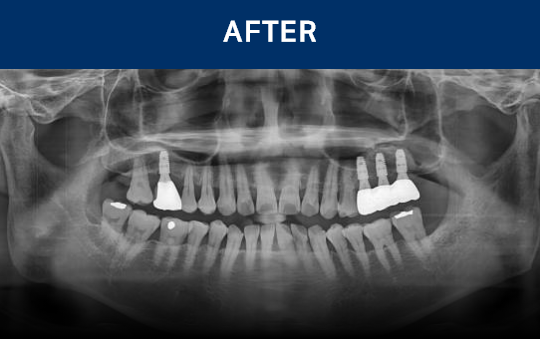

전후가 명확한 결과, 그 결과가

곧 신길플란트치과의 신뢰입니다.

불편함 없이 웃고, 걱정 없이 드실 수 있도록 임플란트로 일상의 편안함을 되찾아드리겠습니다.